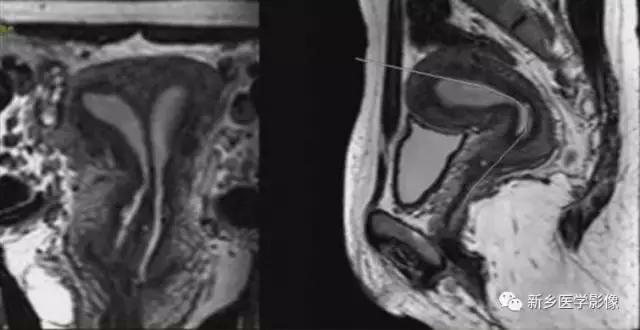

完全型纵隔子宫:短T2信号纵隔贯串宫腔,宫颈管及阴道上段。

MR诊断为完全型纵隔子宫伴阴道纵隔。

完全型纵隔子宫:宫底平坦,纵隔贯串宫腔和宫颈

不完全型纵隔子宫:宫底平坦,纵隔未达宫颈内口水平